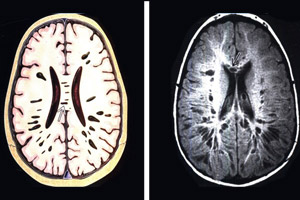

Лечение ТГСК заключается в пересадке стволовых клеток из крови здорового донора в организм больного человека. После пересадки донорские клетки начинают размножаться и производить все ферменты, которых не хватало реципиенту трансплантата. ТГСК рекомендуется проводить как можно раньше, особенно до того, как в головном мозге разовьются значительные накопления.